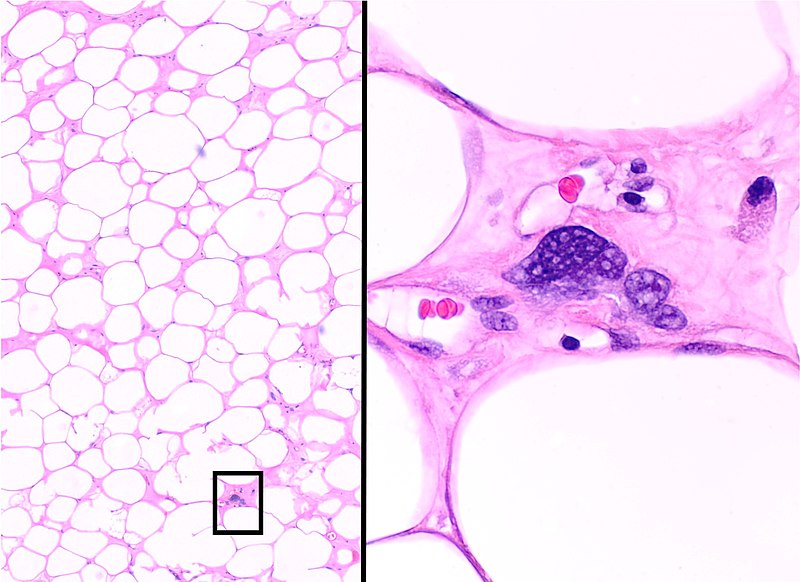

Definitive diagnosis of lipoma is made by pathology showing a well circumscribed mass composed of benign adipocytes.

Lipoblasts are the characteristic cells seen in liposarcoma.